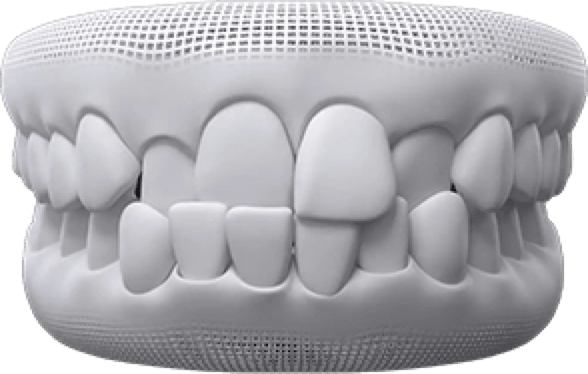

Crowded teeth are a condition where you do not have enough room for your teeth to fit normally. This can cause plaque or tartar and other harmful bacteria to build up as it is harder for you to brush and floss well.

Gaps between teeth are when there is extra space between two or more of your teeth. This can cause pockets between your teeth and gums, causing food to get stuck and making them tender and sore. This might also lead to gum disease.

An open bite is when your upper and lower teeth don't touch when you close your mouth. An open bite can make it hard for you to chew or difficult to bite even the most common of foods like apples.

An underbite is when you close your mouth, and your lower front teeth are in front of your upper teeth. In many cases, this is actually a problem with your lower jaw being too far forward. An underbite can make it hard to chew properly and speak clearly, and it might cause your teeth to wear down more quickly.

An overbite is when your upper front teeth overlap with your lower front teeth. Most people have at least a little overbite. When your overbite is too large, your dentist might tell you that you have a deep bite. This can cause problems, from your teeth wearing down to pain in your jaw.

A crossbite is when you close your mouth, and yet some of your upper teeth sit inside your lower teeth rather than on the outside. A crossbite can make your teeth wear down or chip. It can also make your gums start to recede or make little notches above your gum line. This kind of damage can lead to painful gum problems or even bone loss.